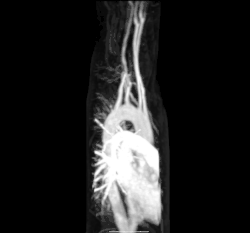

Arteria subclavia aberrante mediante TAC. (1) Tráquea, (2) Esófago, (3) Arteria subclavia aberrante -